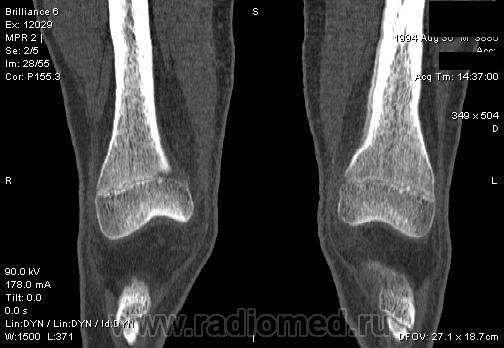

Мальчик 15 лет. Несколько месяцев назад начали беспокоить боли в коленных суставах. Травмы не было. Ребёнку был выставлен диагноз: болезнь Шлаттера, назначено лечение. На фоне лечения отмечалось значительное усиление болей, боли локализовались в левом коленном суставе. При дообследовании выявлена следующая рентгенологическая картина. Наши рентгенологи настаивают на срастающемся переломе. Но: 1) перелом без травмы? 2) бедро так не ломается

В голову приходит остеомиелит или опухоль.

Линейный периостит, уже должен был рентгенологов насторожить.

Локальный гиперостоз, выраженный болевой синдром, структура губчатого вещества диафиза не изменена наводит только на остеойд-остеому.

Я бы на первое место поставила патологическую перестройку, так называемый, стрессовый перелом. Мальчик чем-нибудь занимается?

Согласна с Ola-la - рентгенологическая картина более всего соответствует стрессорному перелому, хотя для него характерна локализация в б/берцовой кости. Меня однако, смущает и настораживает клиника - это как раз тот случай, когда я бы не дала 100% гарантии, что так не может манифестировать остеосаркома... Поскольку другие методы (МРТ, сцинтиграфия) вряд ли помогут, я бы взяла пациента на короткое ( 2недели - месяц) динамическое наблюдение.

Да, на мой взгляд, состояние после обычного "травматического перелома" (трещина), не думаю, что имел место "патологический перелом", так как костная ткань "патологически изменена" минимально. "Перистальная реакция"локальная тоже есть, на КТ "локальная  зона склероза" - все это свидетельствует именно об этом. Хотя в памяти у меня хорошо отложился Ваш последний случай о локальном утолщении кортикального слоя, когда "яйца в гнезде" еще не было. То, что анамнестически "травмы не было" - ничего не значит. Вы, по всей видимости, тоже часто встречались с такими случаями, когда ребенок не акцентировал внимание на "травме", как таковой, хотя клиника есть, боль есть. Конечно, рентгенограммы - не дай бог - ни скиалогии, ни структуры.